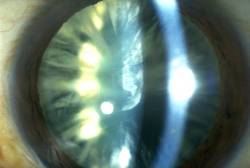

I VARI TIPI DI CATARATTA

Col tempo, la struttura del cristallino tende a variare, per cause ancora in parte imprecisate, perdendo la trasparenza. Quando tale perdita di trasparenza arriva al punto di diventare grossolanamente visibile o di dare un calo della vista, si parla di CATARATTA.

Come detto in precedenza, la partecipazione delle varie zone del cristallino al formarsi delle opacità è un fenomeno che viene sfruttato per un tipo di classificazione.

Distingueremo quindi:

- Cataratta nucleare se è coinvolto principalmente il nucleo del cristallino;

- Cataratta corticale se è coinvolta principalmente la corteccia del cristallino;

- Cataratta sottocapsulare, soprattutto posteriore, se è coinvolta principalmente la capsula.

Esistono ovviamente forme miste, come ad esempio la cataratta cortico-nucleare e la cataratta totale.

Questa distinzione in vari tipi non è solo accademica: i disturbi visivi e (molto relativamente) le difficoltà tecniche legate all'intervento sono legate infatti al tipo di cataratta.